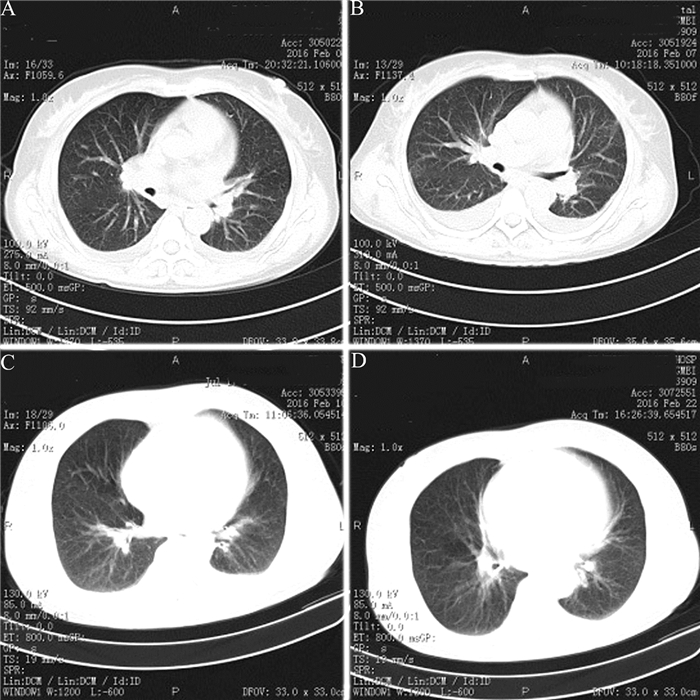

图 1 该例AOSD患者胸部CT检查图 A:左肺下叶少许渗出,双侧少量胸腔积液;B:治疗3 d后双肺肺炎、双肺下叶肺不张病变有所加重;C:治疗8 d后,双侧少量胸腔积液,双下肺炎;D:治疗3周后双侧少量胸腔积液

2016年2月4日胸部CT:左肺下叶少许渗出;左心增大;纵隔、双肺门淋巴结部分钙化;双侧少量胸腔积液(图 1A)。心电图:T波改变。血常规:血红蛋白109 g/L,红细胞3.81×1012/L,白细胞20.50×109/L,中性粒细胞绝对值17.62×109/L,淋巴细胞绝对值1.02×109/L,红细胞比积0.32,血小板291×109/L。血电解质:钠135.24 mmol/L,钙1.83 mmol/L,磷0.63 mmol/L;肝功能:ALT 86 U/L,AST 176 U/L。入院诊断:① 双侧细菌性肺炎并类肺炎性胸腔积液;② 左心增大原因待查;③ 继发性肝损害;④ 低蛋白血症。

予患者头孢曲松钠他唑巴坦钠抗感染以及保肝、补液等治疗,其仍持续发热,咳嗽、咳痰,气促明显。2016年2月7日复查胸部CT无好转、双侧胸腔积液较前增多(图 1B),多次血培养阴性,骨髓穿刺检查提示感染骨髓象、无噬血细胞现象。腹部B超示肝、胆、胰、脾未见异常,RF、抗核抗体、抗核抗体谱等均阴性,CRP 196.58 mg/L,IL-6 1 063 pg/ml,降钙素原2.44 ng/ml,ESR 53 mm/h,且呈进行性升高,铁蛋白>1 500 μg/L。考虑患者持续发热、咳嗽、咳痰,胸部CT提示肺炎,予抗生素治疗效果不理想,伴咽痛,白细胞及中性粒细胞明显升高,肝功能异常,RF和抗核抗体均阴性,虽无典型关节痛、皮疹表现,但根据日本AOSD研究委员会提出的诊断标准需考虑排除AOSD的可能,遂予其甲泼尼龙琥珀酸钠80 mg静脉滴注、1次/12 h,治疗5 d后患者仍有高热,且体温高达40.3℃,复查CT见仍有双下肺炎的表现(图 1C),考虑有可能为糖皮质激素(激素)剂量不够,遂将甲泼尼龙琥珀酸钠改为80 mg静脉滴注、1次/8 h,治疗5 d后患者体温降至正常,改用地塞米松10 mg静脉滴注、1次/12 h,持续治疗4 d后改为口服泼尼松50 mg、2次/日,治疗3周后复查CT见双侧仅有少量胸腔积液(图 1D)。1个月后患者体温平稳,咳嗽、咳痰及气促好转,予其带药出院,泼尼松50 mg、2次/日(其后逐渐减量)。出院后随访2周患者体温正常,无咳嗽、咳痰,无心悸、气促等,继续随访半年,其无不适,情况稳定。